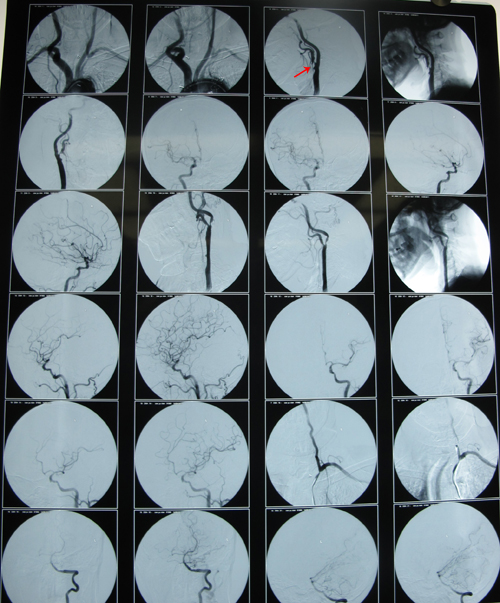

头颅CTA(同煤总医院,2011-5-30):颈动脉硬化性改变(左侧颈内动脉近段管腔中重度狭窄,右侧颈内动脉近段轻度狭窄)。

左侧颈内动脉起始段中重度狭窄,颈总动脉重度狭窄

右侧颈外动脉起始处轻度狭窄

患者手术指征明确(症状+病变),2011年6月24日,协作组张勤奕教授应邀前往同煤总医院为其实施了左侧颈动脉内膜剥脱术。